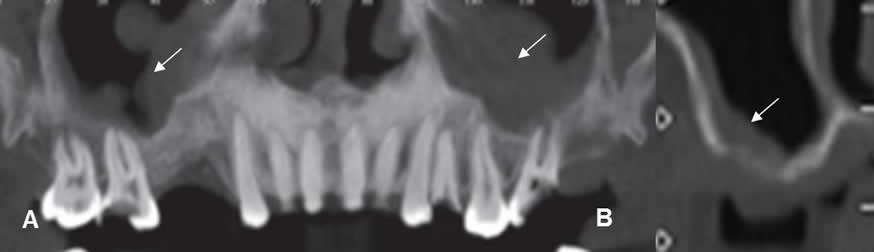

El objetivo principal del estudio preoperatorio por imágenes, es determinar si existe la suficiente cantidad de hueso alveolar, para colocar el implante. Otros son, conocer la exacta localización del canal mandibular y el foramen incisivo, para evitar su lesión durante la cirugía, saber las características de los senos maxilares y determinar las contraindicaciones o patologías asociadas. (Fig 17, 18, 19 y 20). (5, 3, 13).

El trauma del nervio alveolar inferior, ocasiona parestesias en la cara y la perforación del seno maxilar, aumenta la probabilidad de infección o falla del implante. (5, 13).

A: Dentascan reconstrucción coronal. Pérdida de piezas en ambas arcadas maxilares. Se aprecia engrosamiento en la mucosa de ambos senos maxilares, por sinusopatía, que debe ser tratada antes de colocar el implante.

B: TAC reconstrucción transversal. Sinusopatía maxilar, asociada a gran atrofia ósea.